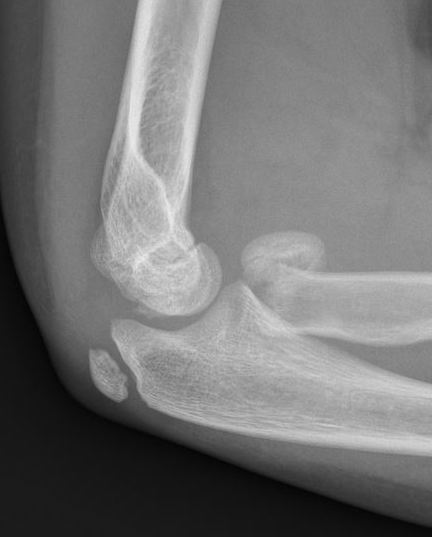

Xray

Displaced and angulated radial neck fracture